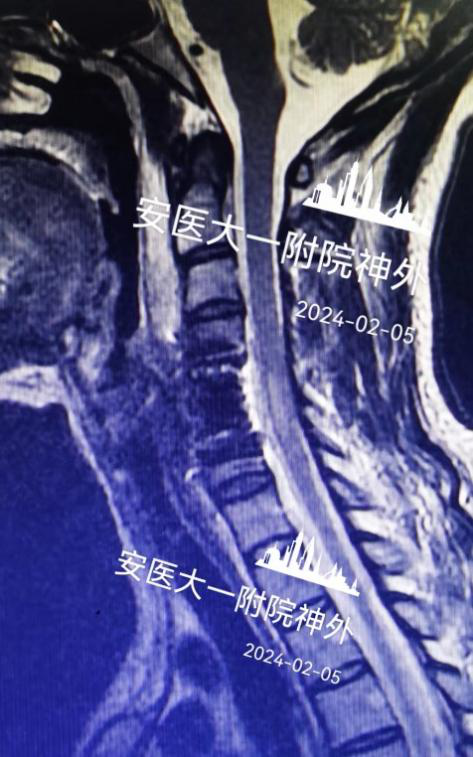

该患者系“右上肢麻木伴左下肢疼痛半年”入院,术前颈椎MR提示C5-6水平脊髓前方囊性占位(图1),囊肿的基底部位于前正中裂至中央管内(图2)。经科室讨论,采用显微镜下颈前经椎体入路脊髓内肠源性囊肿切除术。术后第四天复查磁共振见囊肿全切,无残留(图3),术后颈椎X线片显示内固定位置良好,颈椎曲度理想(图4.5)。术后患者恢复良好,术后第四天患者自己可以下床行走,四肢肌力正常(图6),右上肢麻木稍减退,左下肢疼痛感消失。

图1:肿瘤位于C5.6脊髓腹侧